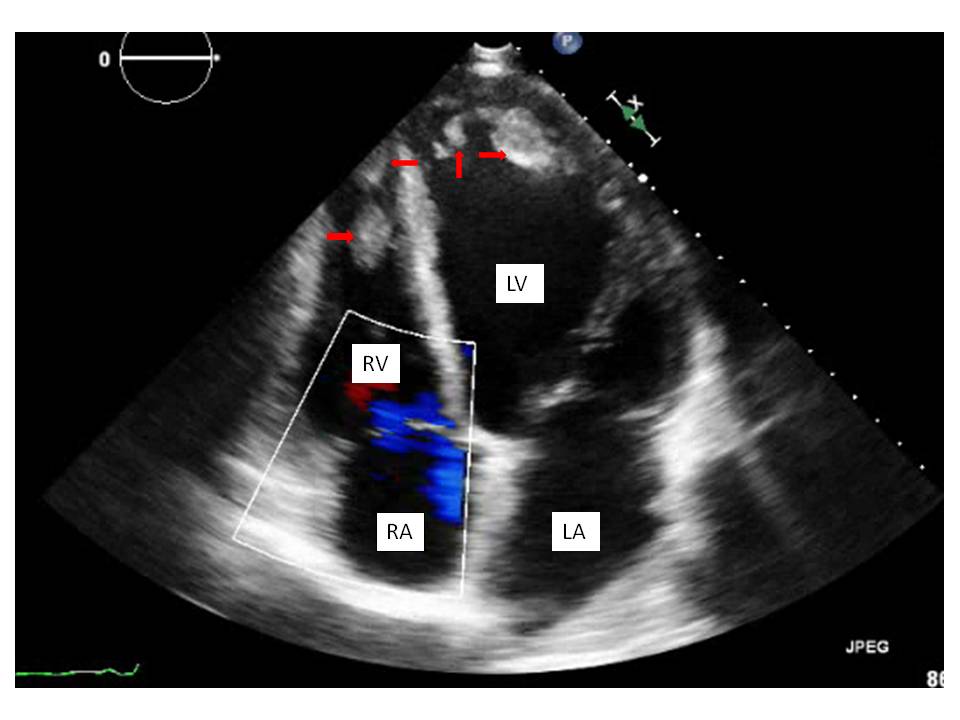

Biventricular thrombi of nonischemic cardiomyopathy

47 year old male with history of alcoholic liver cirrhosis came in with severe bilateral lower extremity pain and new onset acute bilateral limb ischemia. Vitals at admission were stable and physical examination showed clear cut cool bilateral lower extremities below both ankle joints with all the 10 toes being black suggesting gangrene. Bilateral dorsalis pedis and Posterior tibial pulses were not felt and could not be detected with dopplers. A transthoracic Echocardiogram revealed that the patient had an Ejection fraction of 10-15% with diffuse hypokinesis, also were noted multiple biventricular thrombi with the largest in the left ventricle measuring 50x30mm in size extending from anterolateral papillary muscle upto the septal myocardium. Evaluation with a cardiac and aortic catheterization revealed non obstructive coronaries, complete occlusion of the bilateral anterior tibial, posterior tibial and peroneal arteries at the ankle level with zero flow below bilateral ankle joints. No intervention could be performed and hence the patient was at first anti coagulated with heparin and then bridged to Coumadin. Patient was discharged to follow up with orthopedic surgery for bilateral amputations. Biventricular thrombi are generally seen in patients with a pro thrombotic state like anti phospholipid antibody syndrome, heparin induced thrombocytopenia induced thrombosis, hypereosinophilic syndrome. Cases have been reported in patients with viral myocarditis and libman sacks endocarditis. It is generally very rare to see multiple biventricular thrombi in patients with low Ejection Fraction.